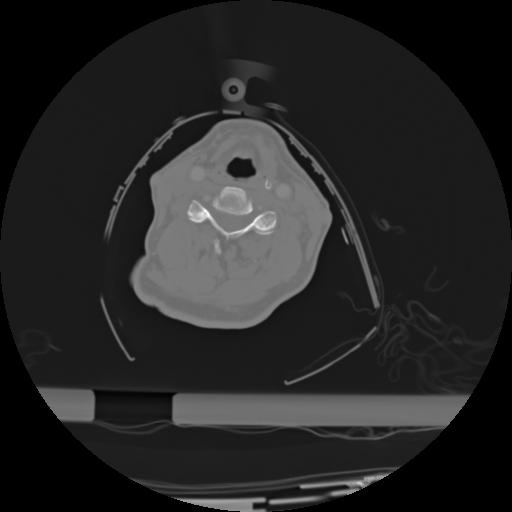

21 ANGIO,CE,Axial,3.0,ANGIO,,